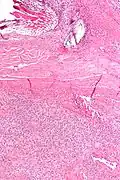

| Micrograph of a solitary fibrous tumor. H&E stain. | |

Solitary fibrous tumor - low magnification. H&E stain. -

Solitary fibrous tumor - high magnification. H&E stain.